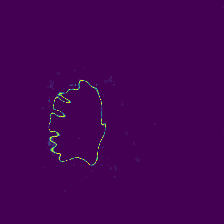

Diffusion models have shown impressive performance for generative modelling of images. In this paper, we present a novel semantic segmentation method based on diffusion models. By modifying the training and sampling scheme, we show that diffusion models can perform lesion segmentation of medical images. To generate an image specific segmentation, we train the model on the ground truth segmentation, and use the image as a prior during training and in every step during the sampling process. With the given stochastic sampling process, we can generate a distribution of segmentation masks. This property allows us to compute pixel-wise uncertainty maps of the segmentation, and allows an implicit ensemble of segmentations that increases the segmentation performance. We evaluate our method on the BRATS2020 dataset for brain tumor segmentation. Compared to state-of-the-art segmentation models, our approach yields good segmentation results and, additionally, detailed uncertainty maps.